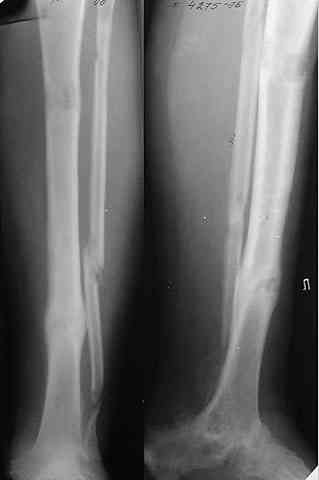

Учитывая ликвидацию голеностопного и подтаранного суставов, надо поберечь остающиеся, чтобы рессорную функцию стопы сохранить по максимуму. Поэтому лучше избегать всякого рода дополнительных вмешательств поблизости от ТЛ и ПК суставов, а то на некоторых схемах чуть ли не их замыкание предусматривается. Опил большеберцовой кости

нарисован слишком горизонтальный, надо пересекать ее параллельно контактной поверхности пятки, наклонно, т.е. больше убрать сзади.

Не адресована другая проблемы - берцово-пяточный блок достигается ценой укорочения конечности на 3-4 см. Поэтому надо предусмотреть что-то для удлинения. У нас в клинике традиционный подход - билокально удлинять большеберцовую кость. Раньше еще и малоберцовую рубили на двух уровнях. Сейчас (спасибо коллегам из форума) пользуемся только